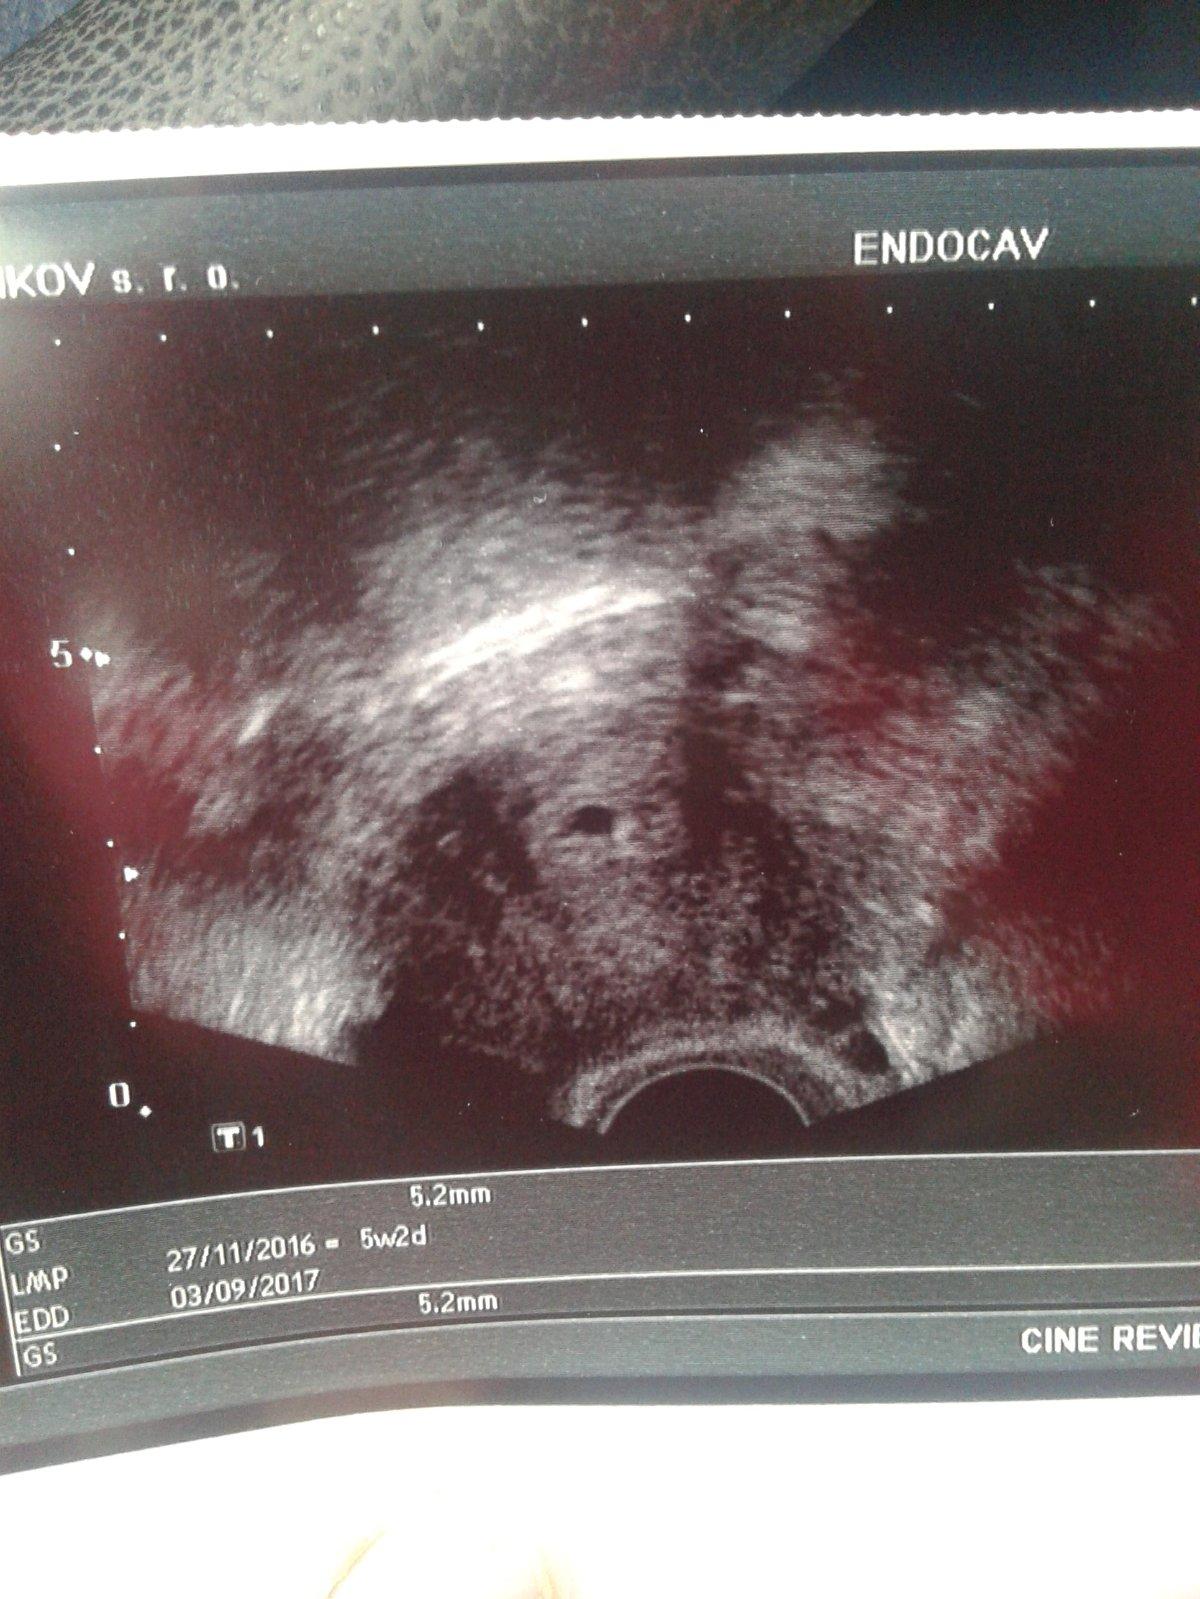

Na prvni fotce 5+2tt (vylouceno mimodelozni a byl videt zloutkovy vacek ) druha fotka 7+2tt uz krasne bilo srdicko 🙂 je pravda, ze zalezi na utz doktora, ale me v tech 5+2tt ani nenapadlo, ze by bylo srdicko, tak budte holky v klidu, do 8tt casu dost 😉

Toto je ma fotka 5+2

Vypada to jako prstynek a jdou videt 2 křizky ze neco měril..

Holky prosiiim.co myslite na ten ultrazvuk ze tam.je teda videt???

@sukubka je to urcite v poradku, akorat to ma hodne priblizene 🙂